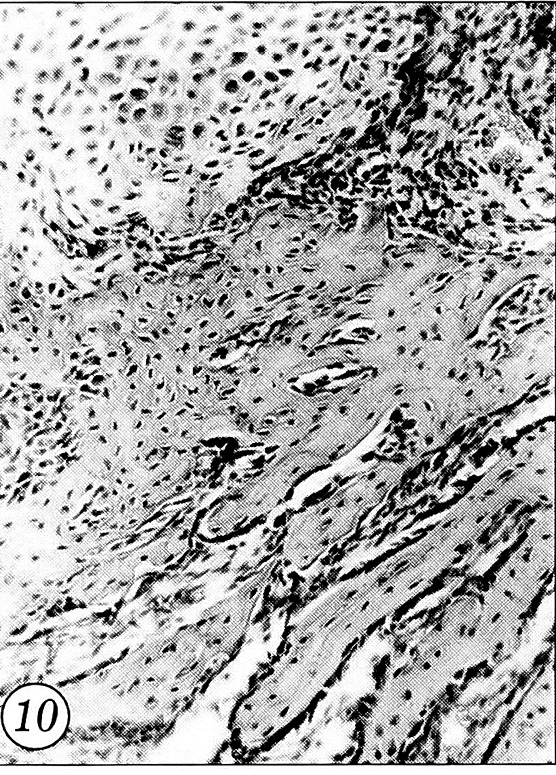

У животных контрольной группы в этот срок формировалась лишь небольшая первичная мозоль, отмечалось наличие хрящевой ткани, обнаруживались многочисленные остеобласты (рис. 10).

Рис. 10. Новообразованная костная и хрящевая ткань костной мозоли. 14-е сутки после перелома, контрольная группа (окраска гематоксилином и эозином, об. 10, ок. 10).